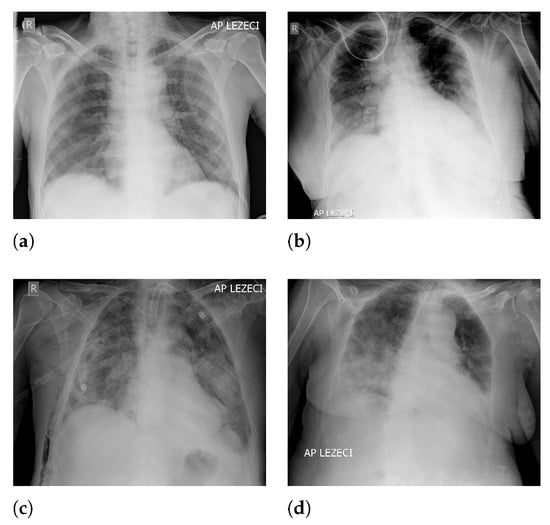

An overview of image classes has been presented in Figure 1, where each class is represented with a X-ray image.

Figure 1. Examples of X-ray images contained in the dataset: (a) A mild clinical picture; (b) moderate clinical picture; (c) severe clinical picture; and (d) critical clinical picture.